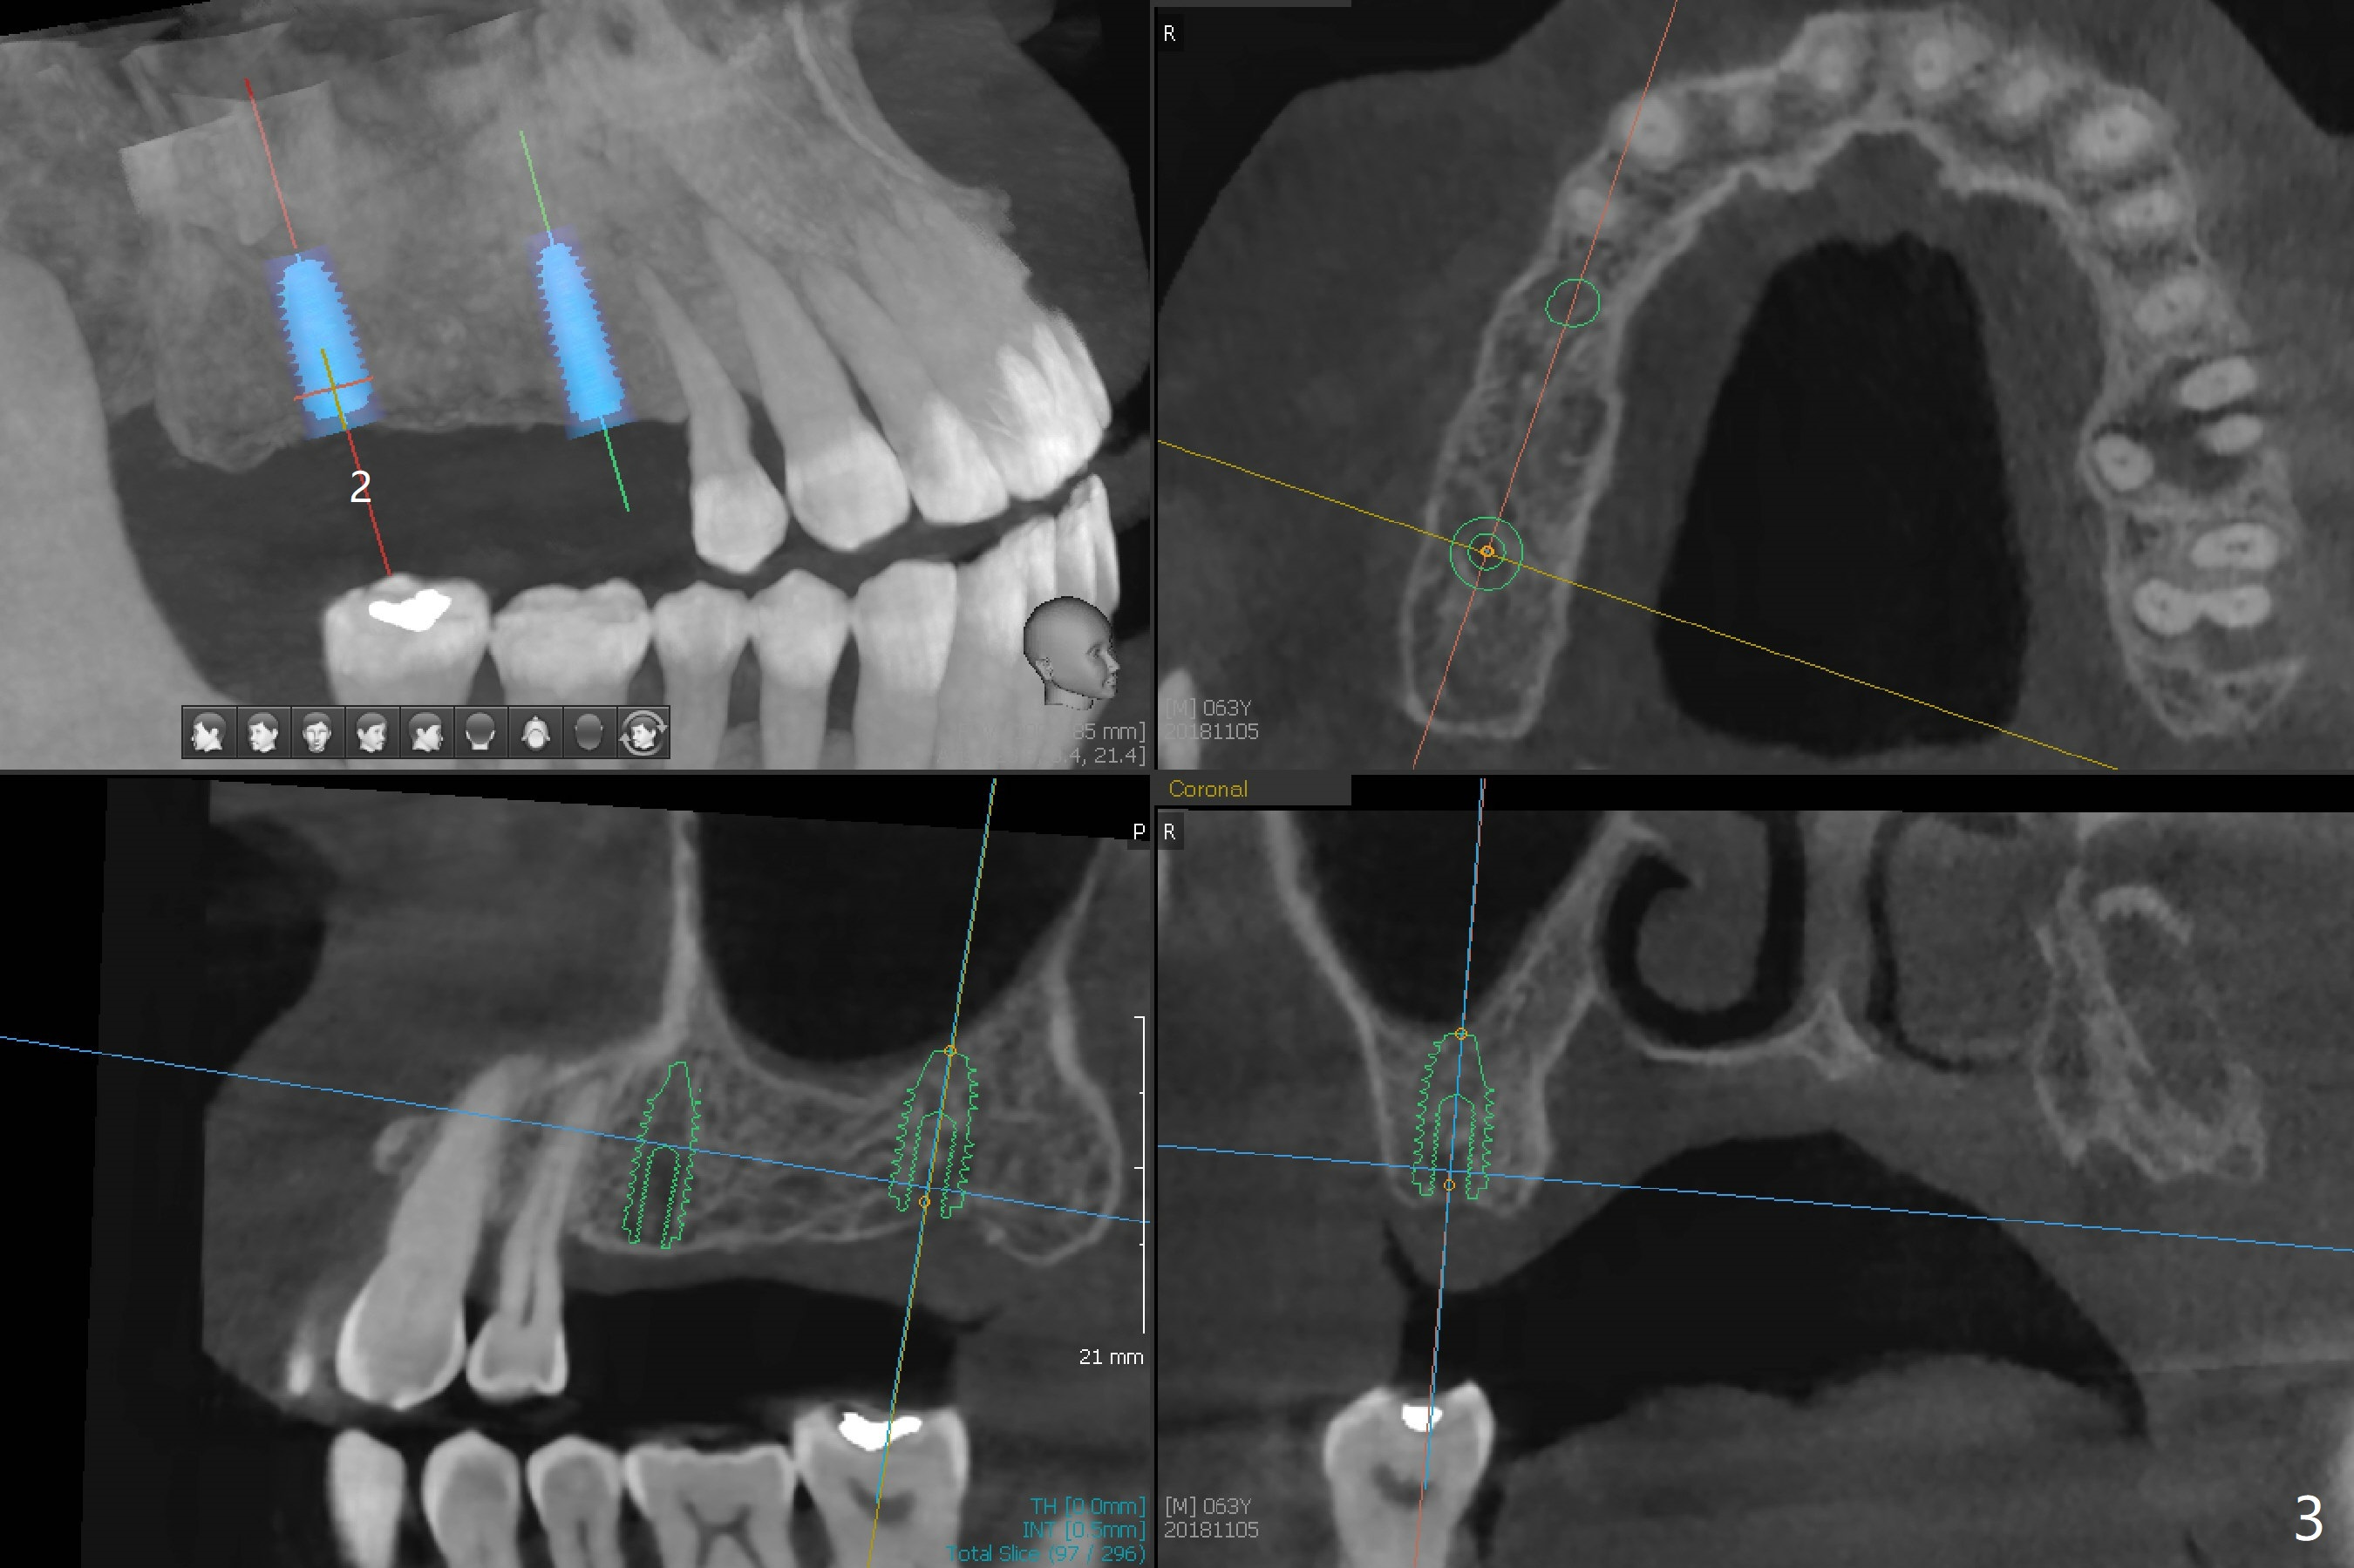

A 63-year-old man lives out of state and returns to office for scaling with chief complaint of occasional upper left pain (#14, Fig.1). After discussion, he agrees to have implant restoration in the upper right quadrant (#2-4). It appears that a 3-unit FPD is appropriate (Fig.2,3). When the teeth #14 and 19 fail, immediate implants will be placed (Fig.4-6).